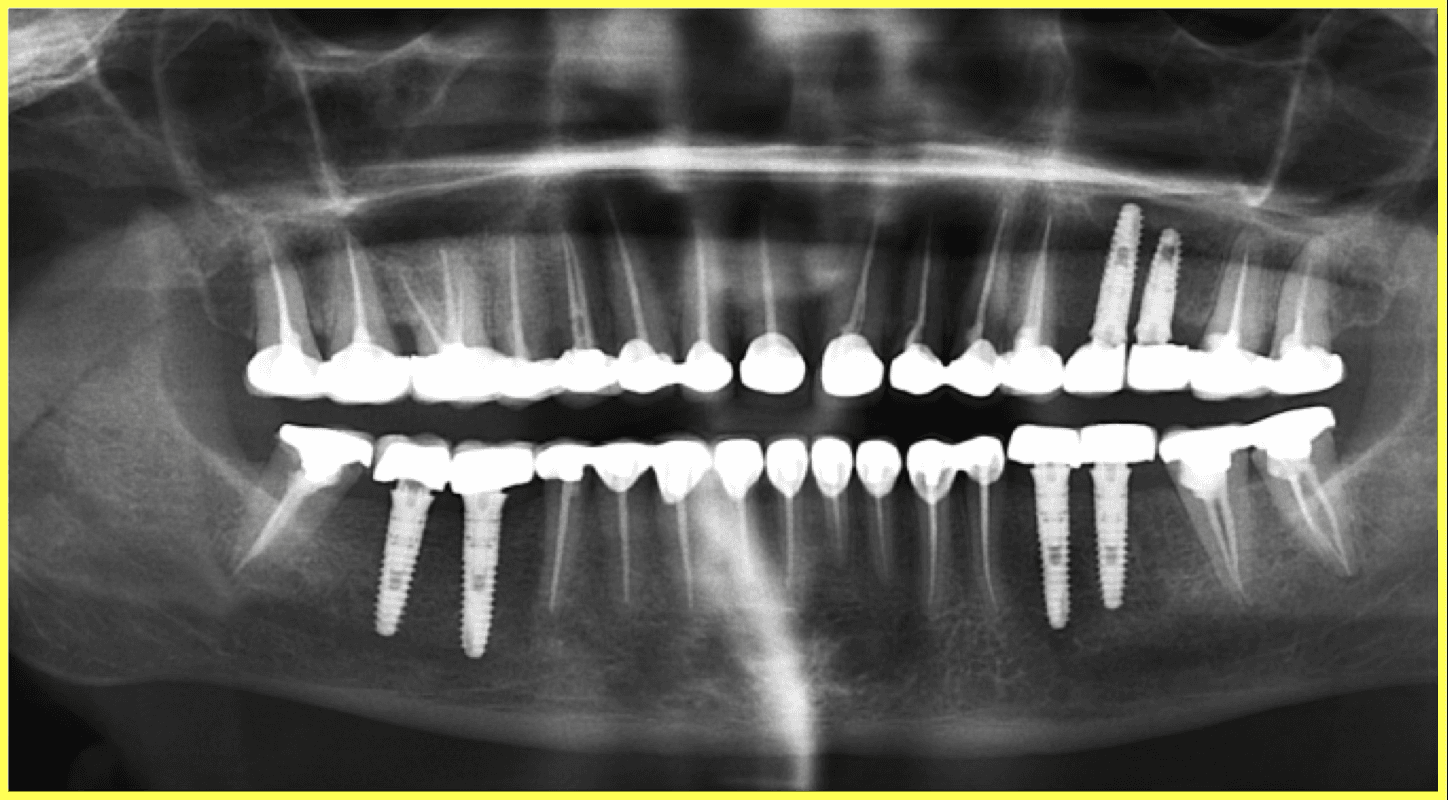

A 57-year-old female patient visited our dental center complaining of multiple missing and attrited teeth. On examination, patient had missing teeth 25, 26, 35, 36, 45 & 46 with grade 3 attrition. Treatment included impression-based muscle deprogrammer, Dio implants placement, PFM crowns for remaining attrited teeth, and delayed implant loading after 3 months.

Comprehensive oral examination with OPG X-ray. Patient presented with multiple missing teeth (25, 26, 35, 36, 45, 46) and severe attrition on remaining teeth. Muscle deprogrammer was fabricated and delivered.

Strategic placement of 6 Dio dental implants in the regions of missing teeth using precise surgical protocols.